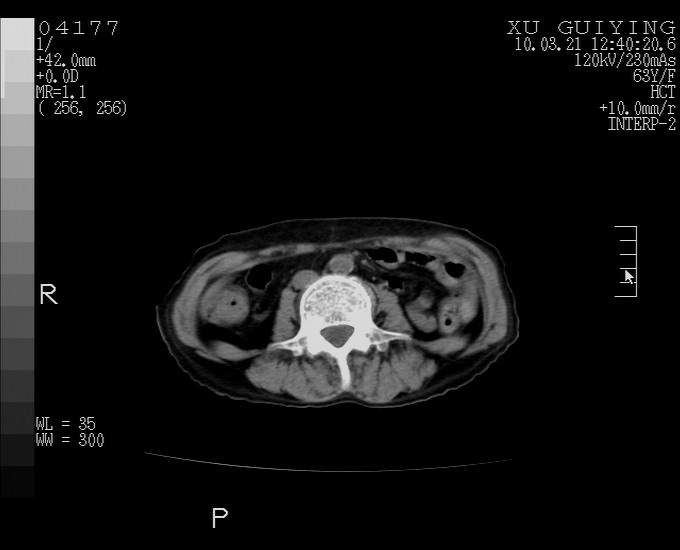

标题: CT25230:女,63岁,萎缩性胃炎病史,患者明显黄染,不能进 [打印本页]

标题: CT25230:女,63岁,萎缩性胃炎病史,患者明显黄染,不能进

怎么没有增强呢?胆囊那么大,密度有些高啊。

慢性胆囊炎,胆囊占位不排除,建议增强或彩超。

考虑胆囊炎 不除外泥沙样结石

胆囊体积增大,胃窦壁增厚

胆囊体积增大,密度不均匀,结石不除外;胃壁增厚,考虑胃癌,建议增强。

胆囊体积增大,密度增高,较均匀,外缘也较光滑,应考虑胆囊炎。因为胃未充盈,不好说壁增厚。肝左叶及脾门处见低密度灶,有可能是血管瘤,不排除囊肿。建议超声检查或强化。